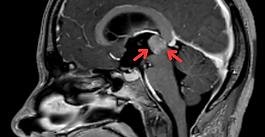

Talamik Glioma

Tanı: Talamik Gliom Konum: Talamus (beynin derin yapılarında, duyu ve motor yolları ile ilişkili) Operasyon Öncesi ve Sonrası Görüntüleme